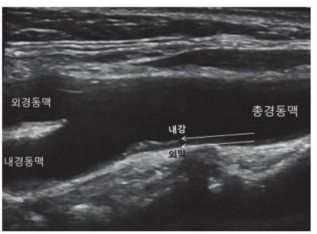

- 경동맥 초음파는 어떤 검사입니까?경동맥 에코는 심장에서 머리로 올라가는 동맥을 직접 초음파로 관찰하게 되는 것입니다.

심장에서 머리로 올라가는 동맥을 초음파로 보는 검사입니다① 혈관벽(Intima-mediathickness(IMT) 두께가 0.9mm이상으로 두꺼우거나 정상치의 75th percentile 이상이면 이상으로 간주합니다.② 혈관의 혈전(plaque)이 최근 혈관벽의 두께보다 더 중요한 의미를 가지는데 주변벽보다 50% 이상 두껍거나 1.5mm 이상 혈관벽의 두께를 나타내면 plaque가 있는 것으로 보입니다. 두께도 중요하지만 떨어져 가면 뇌졸중이기 때문에 혈전이 어떤 형태인지도 중요합니다.③ 혈관이 70% 이상 좁아진 경우에는 혈관 시술을 고려해야 합니다. stent를 넣거나…

- Plaque definition 1) focal wall thickening that is ≧ 50% greater than the surrounding vessel wall, 2) Focal region with an the surrounding vessel wall, 2) Focal region with an IMT